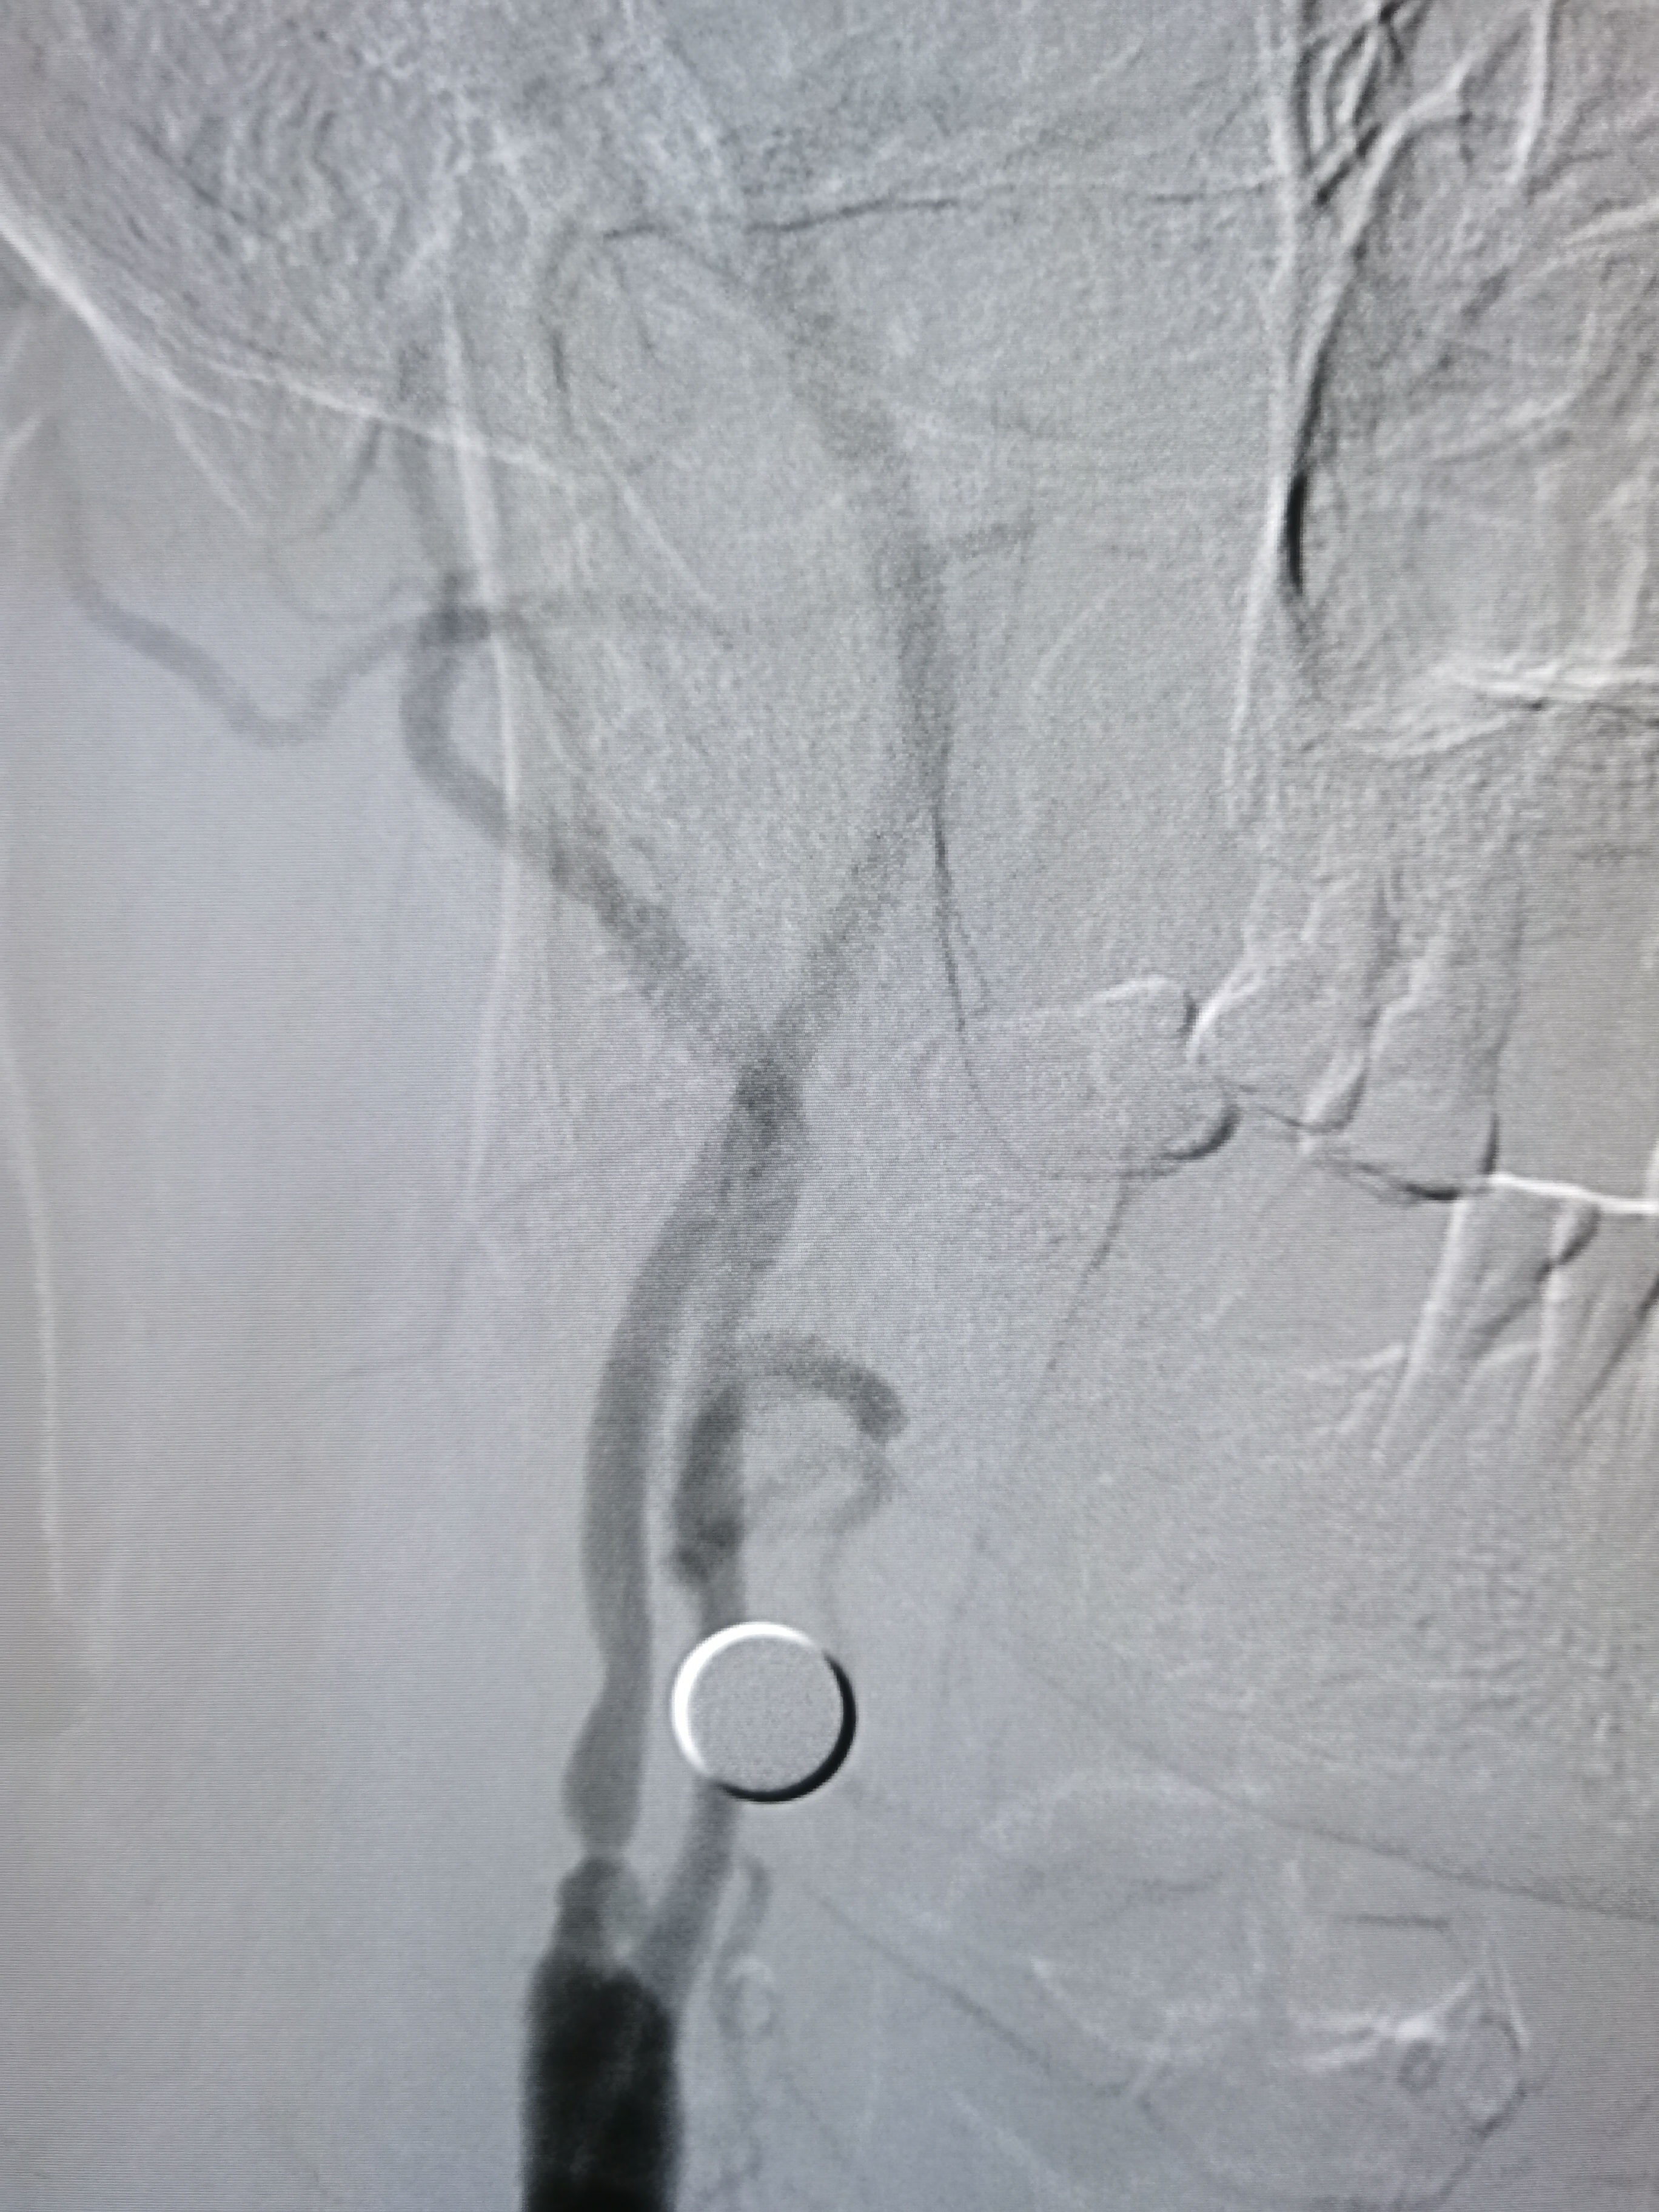

左侧锁骨下动脉硬化,左椎优势。

基底动脉正常。

右椎动脉劣势。

颅内段显影可。